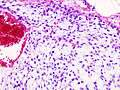

| Histopathologic image of chondrosarcoma of the chest wall. Surgical resection of recurrent mass. H & E stain. | |

Physicians grade chondrosarcoma using several criteria, but particularly on how abnormal the cancerous cells appear under the microscope, and the growth rate of the tumors themselves, both of which are directly linked to the propensity of the cancer to invade locally, and to spread widely to distant organs and sites in the body (called metastasis).

Grade 1 chondrosarcoma grows relatively slowly, has cells whose histological appearance is quite similar to cells of normal cartilage, and have much less aggressive invasive and metastatic properties. Grades 2 and 3 are increasingly faster-growing cancers, with more varied and abnormal-looking cells, and are much more likely to infiltrate surrounding tissues, lymph nodes, and organs. Some, but not all, authorities and medical facilities assign a "Grade 4" to the most anaplastic, undifferentiated cartilage-derived tumors.